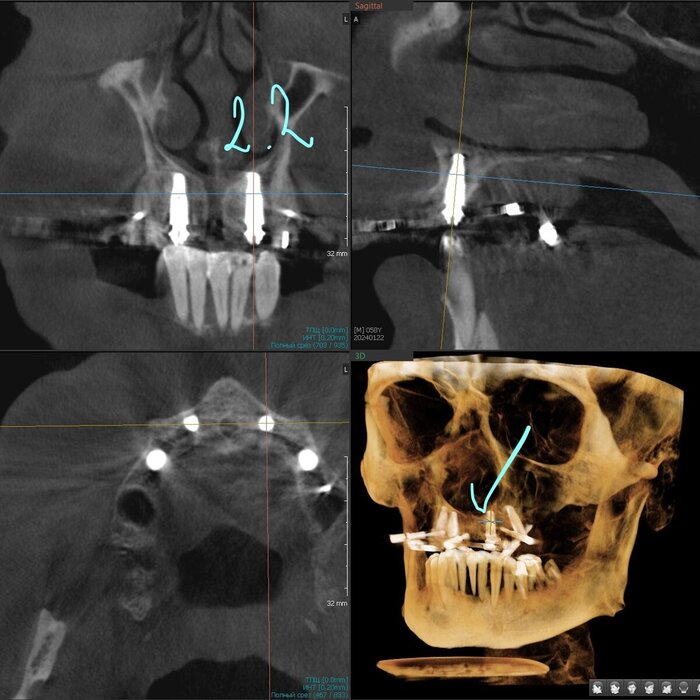

Примерка временного протеза "всё на 4-х"

Постановка на воске.

Временный протез "всё на 4-х", постановка на воске